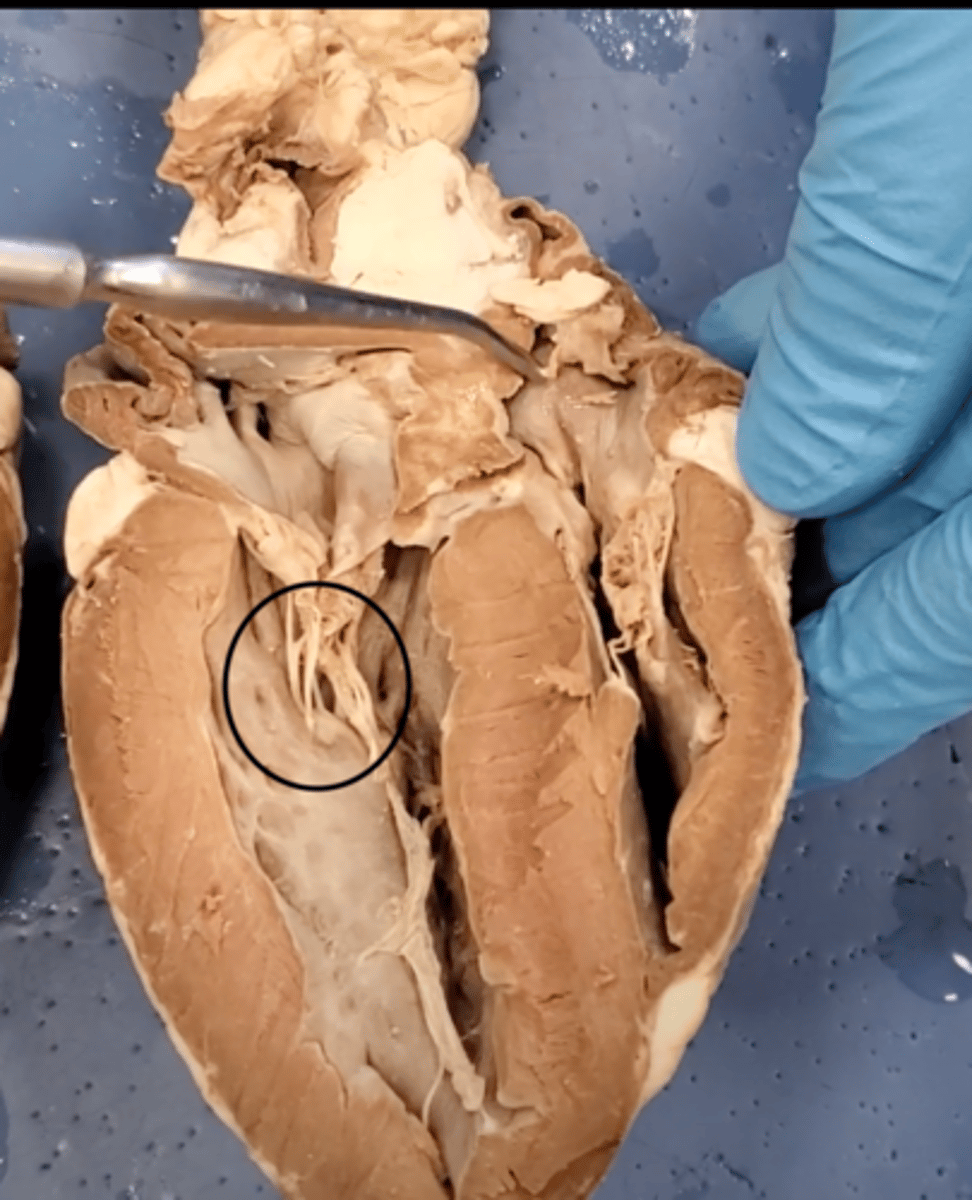

Tricuspid Valve (Right Atrioventricular Valve)

1-valve

Bicuspid valve (Left Atrioventricular Valve)

2-valve

Pulmonary Semilunar Valve

3-valve

Aortic Semilunar Valve

4-valve

Right Atrium

1-chamber

Left Atrium

2-chamber

Right Ventricle

3-chamber

Left Ventricle

4-chamber

bicuspid valve (dissection)

tricuspid valve (dissection)

aortic semilunar valve (dissection)

located between the left ventricle and the aorta

chordae tendineae (dissection)

thin bands of fibrous tissue that attach to the valves in the heart and prevent them from inverting